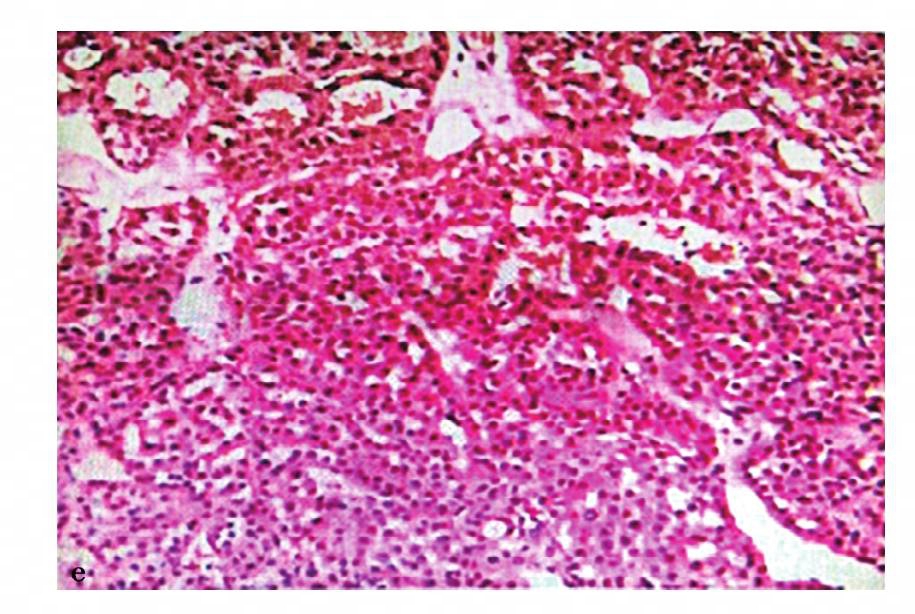

图15 e,病理诊断:肾嗜酸细胞腺瘤